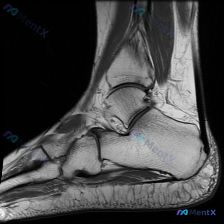

看到这个病例,核心矛盾很典型:临床提示关注软骨异常,但只提供了单张踝关节矢状位T1加权MRI,我整理了分析思路和大家分享。 一、病例核心影像信息 这是一张踝关节矢状位T1WI MRI,我们先整理所有客观发现: 1. 骨骼结构:胫骨远端、距骨、跟骨、舟骨、骰骨形态完整,骨皮质连续,骨髓信号均匀正常高信...